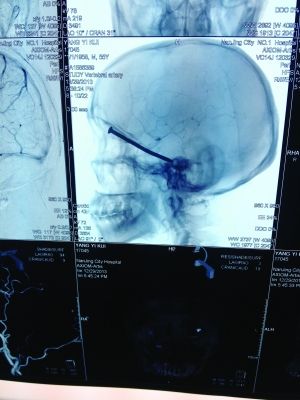

CT投影

前幾天,市民楊先生在家翻新地板時(shí),眼中突然飛入“異物”。去醫(yī)院檢查,發(fā)現(xiàn)這“異物”竟是一根長(zhǎng)達(dá)8厘米的鐵釘!好在鐵釘錯(cuò)開了楊先生頭部的各種大血管,醫(yī)生得以順利將其取出。

CT投影結(jié)果,把大家嚇了一跳:楊先生腦子里居然有一根長(zhǎng)釘,從眼眶一直“伸”到了接近后腦勺的位置!鐵釘細(xì)長(zhǎng)略帶彎曲,長(zhǎng)達(dá)8厘米。根據(jù)推測(cè),鐵釘應(yīng)該是從上眼眶的縫隙中飛入,一直插進(jìn)腦顱中,末端還有一個(gè)小小凸出的釘帽。